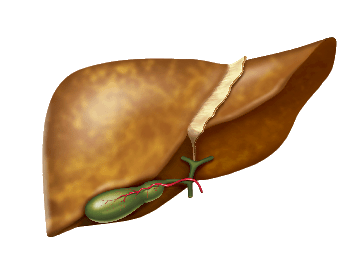

Як розвивається процес руйнування печінки?

Основні стадії розвитку

захворювань печінки

Основні стадії

розвитку захворювань

печінки

накопичення

жиру

в гепатоцитах

надмірне

освіта

вільних

радикалів

і розвиток

запалення

загибель

гепатоцитів

і їх заміщення

рубцевої

тканиною

необоротне

порушення

структури

і функцій

печінки